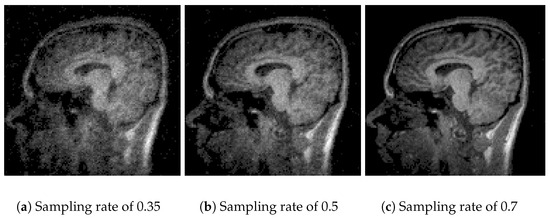

In Figure 4, the performance of Algorithm 1 using the discrete wavelet transform (DWT) is observed. With a sampling rate of 35% (Figure 4a), the reconstruction is poor and lacks information due to the use of one coefficient in the Waverec command, which creates reduced square wavelets. By increasing the sampling rate to 50% (Figure 4b) and 70% (Figure 4c), the image quality improves, but spaces without information remain. The results of Algorithm 1 show a PSNR of 14.07 dB and an SSIM of 0.22 (Table 2). At a sampling rate of 50%, the values improve slightly, reaching a PSNR of 15.45 dB and an SSIM of 0.32 (Table 3). At a rate of 70%, PSNR values of 17.70 dB and an SSIM of 0.45 (Table 4) are achieved. The compression efficiency reaches 0.92, indicating that the stored data are closely similar to the original while maintaining a RMSE of 13%.

Figure 4. Comparative images for Algorithm 1.